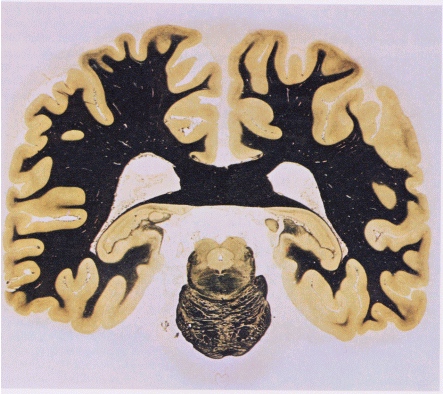

Schneidet man das Gehirn im Bereich der Ohren senkrecht auf, dann ergeben sich die folgenden Schnittbilder; auch hier erkennt man beide Male sehr schön oben unter dem Scheitel einen tiefen Einschnitt, der die beiden Hemisphären voneinander trennt; weiter unten im Schädel ist dann wieder jenes 'Breitbandkabel', der corpus callosum, zu erkennten:

Die beiden Präparate wurden mit einem Farbstoff behandelt, der die Myelinhüllen der Nervenfasern schwärzt. Die aus Nervenfasern bestehende weiße Substanz erscheint deshalb schwarz. Die vorwiegend aus Zellkörpern gebildete graue Substanz der Gehirnrinde bleiben ungefärbt. Die leeren Gebiete im Innern zeigen die Lage der flüssigkeitsgefüllten Gehirnkammern.